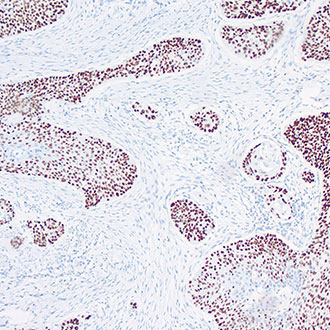

IHC

免疫组织化学(IHC)